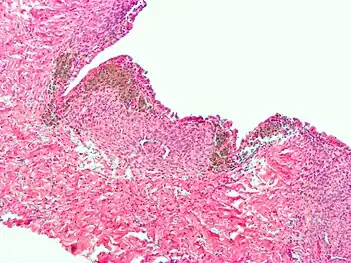

Micrograph of the wall of an endometrioma. All features of endometriosis are present (endometrial glands, endometrial stroma and hemosiderin-laden macrophages).

Histopathology

For a histopathological diagnosis, at least two of the following three criteria should be present:[88]

- Endometrial type stroma

- Endometrial epithelium with glands

- Evidence of chronic hemorrhage, mainly hemosiderin deposits

Immunohistochemistry has been found to be useful in diagnosing endometriosis as stromal cells have a peculiar surface antigen, CD10, thus allowing the pathologist go straight to a staining area and hence confirm the presence of stromal cells and sometimes glandular tissue is thus identified that was missed on routine H&E staining.[89]